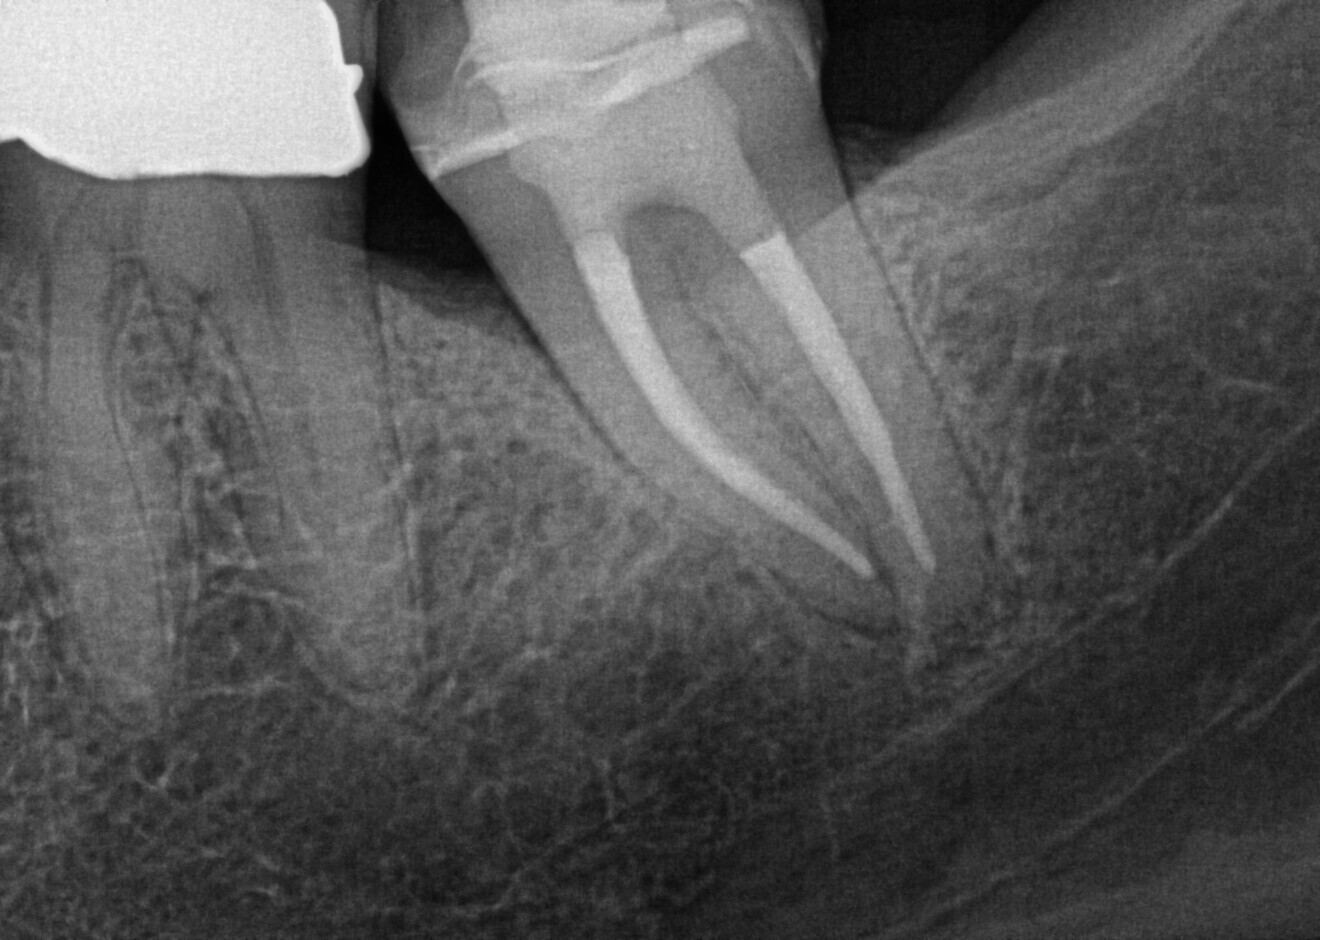

The post-op radiograph shows the tooth after endodontic preparation with HyFlex EDM OGSF files, ensuring gentle cleaning in complex canal anatomy, and obturation. (Image: Dr Sabine Remensberger)